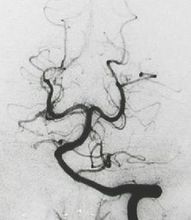

椎动脉造影

椎动脉

椎动脉颈动脉

椎动脉解剖图

椎动脉图片解剖

椎动脉图片